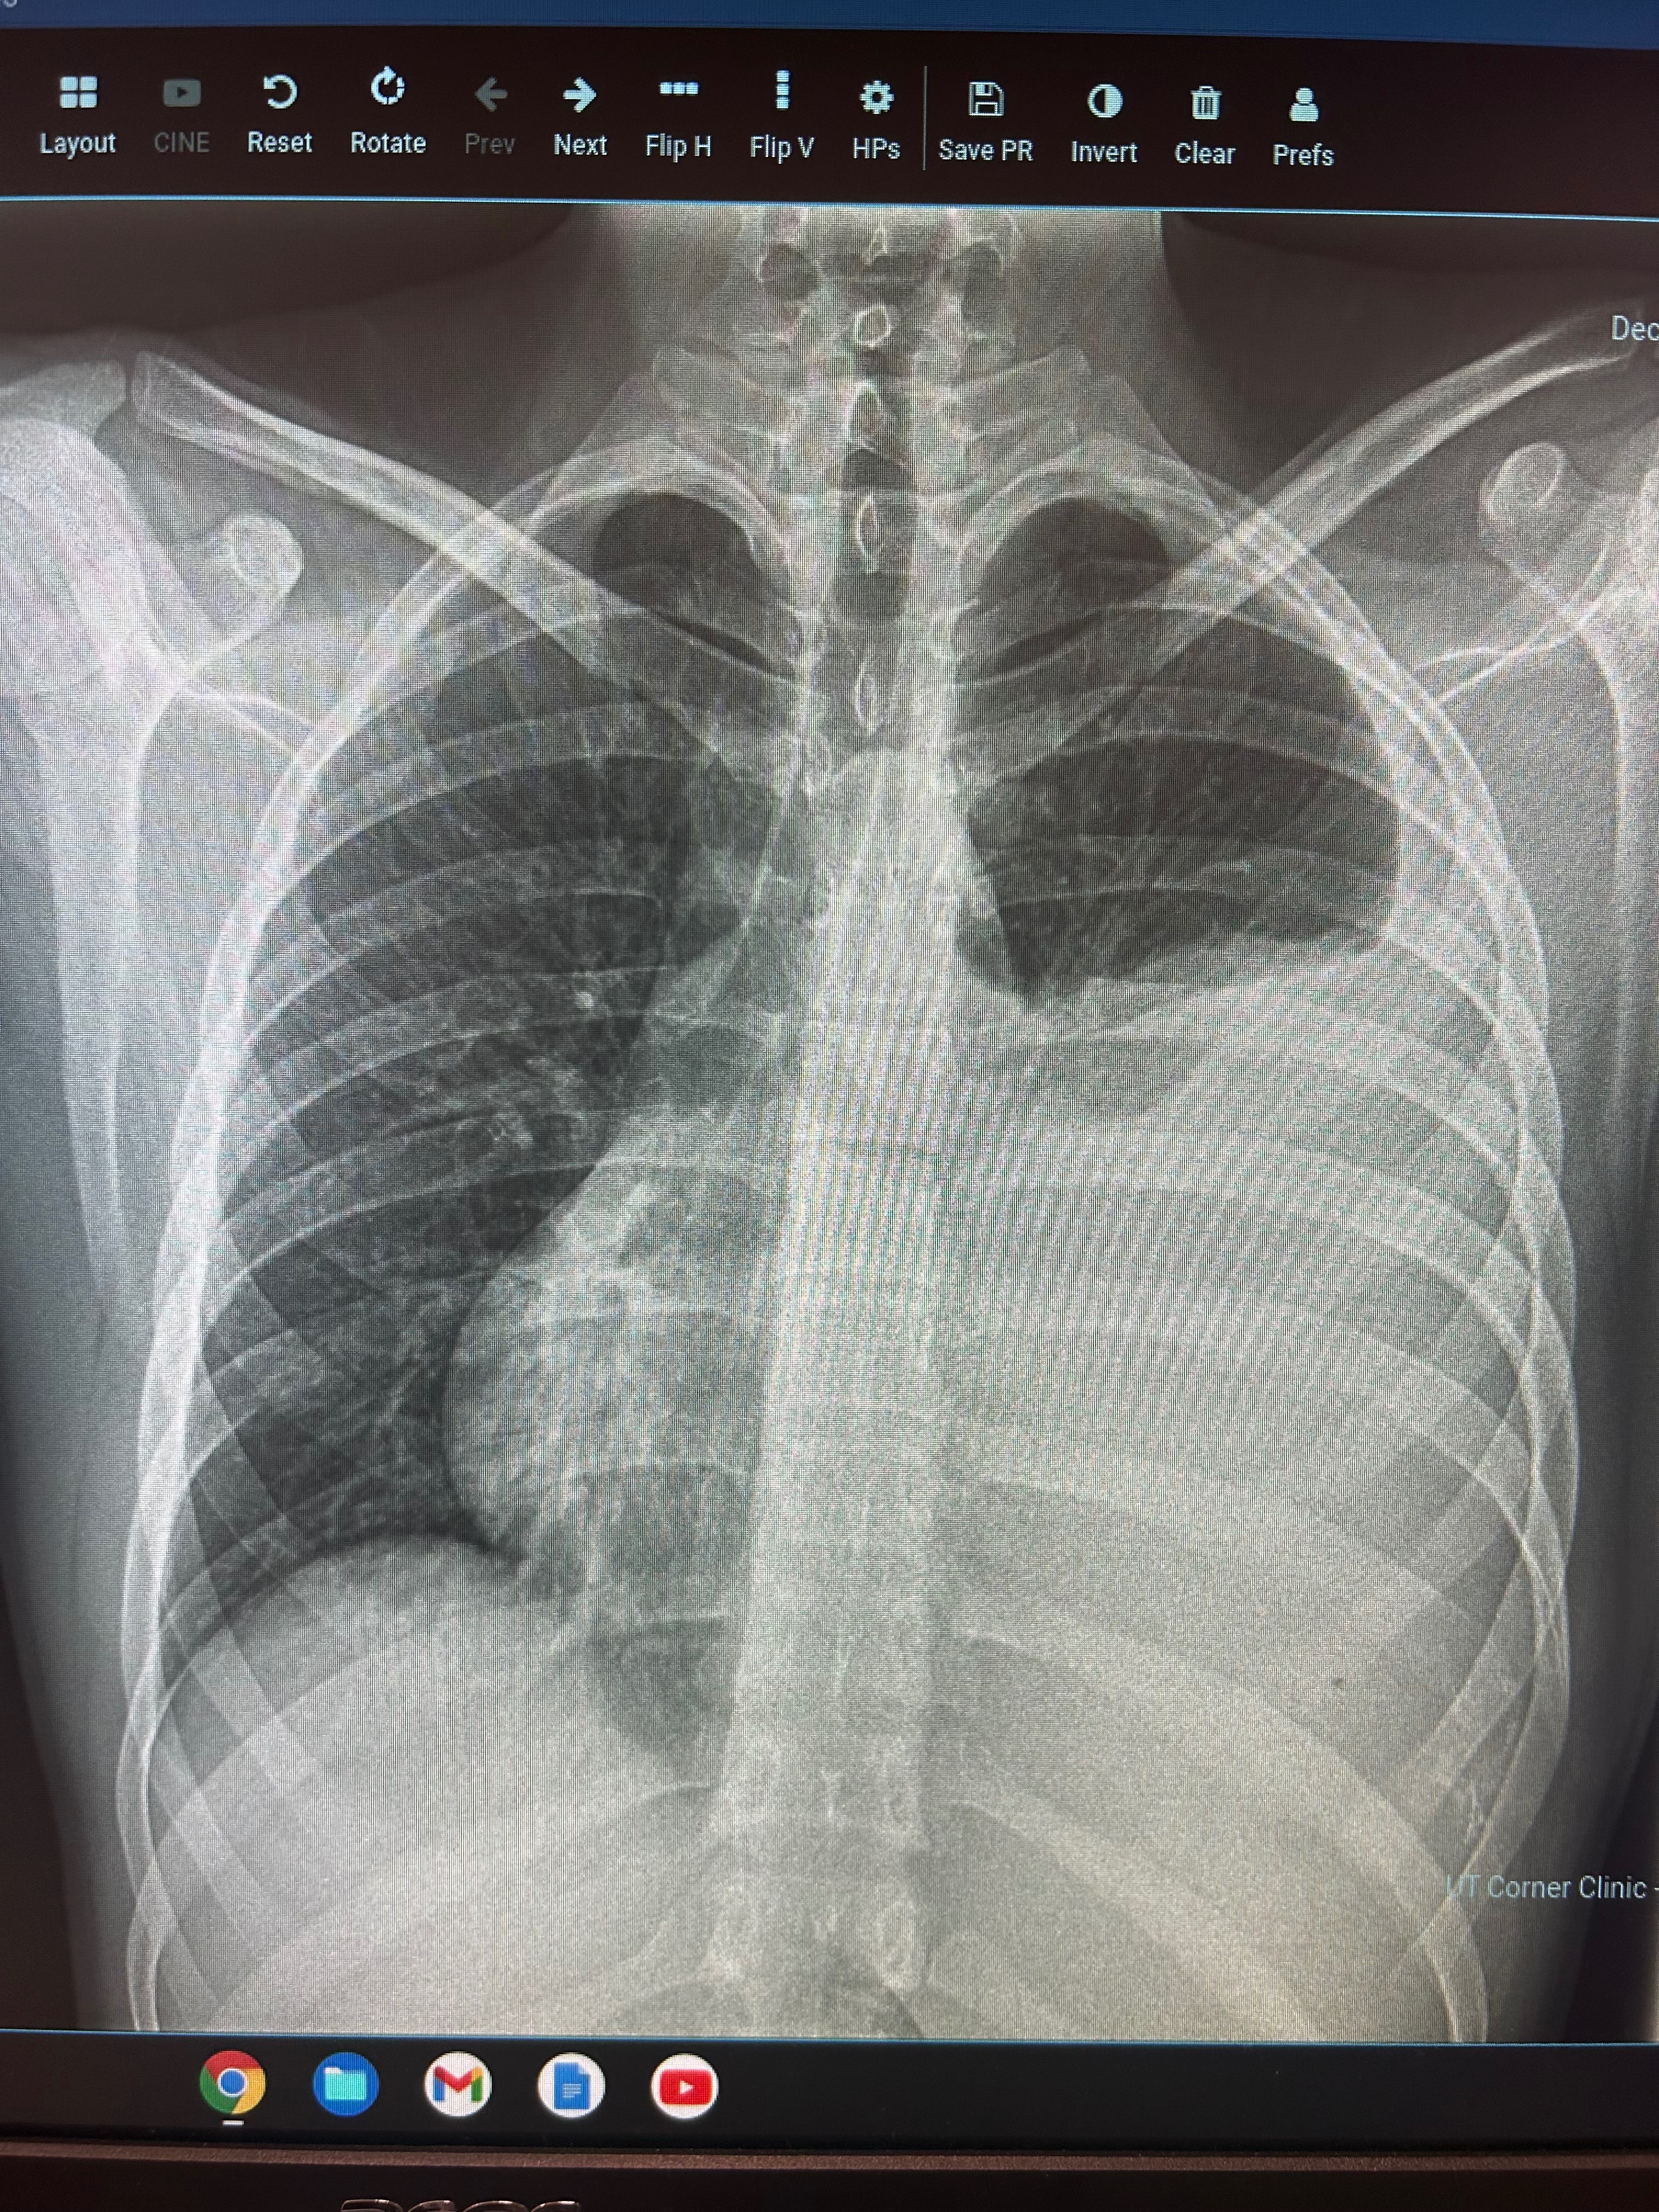

The Campbell family recently received the devastating news that their oldest son, Kody, who is only 19 years old, has been diagnosed with sarcoma cancer. This aggressive tumor has already destroyed one of Kody’s rib bones and is overtaking his lung, making it difficult for him to breathe and causing him to retain a significant amount of fluid. The suddenness and severity of Kody’s diagnosis have turned the Campbell family’s world upside down, bringing with it not only emotional pain but also overwhelming financial challenges.